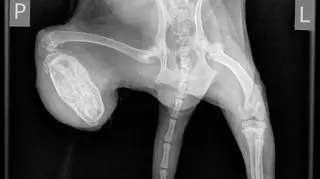

Zwierzaki zostały dokładnie przebadane, zważone i zmierzone. Lekarz wykonał im też zdjęcia rentgenowskie, na których widać małe, kostne kikuty. - Istnieje możliwość, że tylne łapy odgryzła im ich własna matka. Zwierzaki trzymane w stresogennym otoczeniu często się okaleczają, dochodzi do różnych, patologicznych zachowań - mówi Karbowiak. Weterynarz stwierdził też u lisków infekcję w ranach po odgryzieniu, gorączkę i kaszel. Zalecił antybiotyk.

Małgosia nie ma obu tylnych łapek